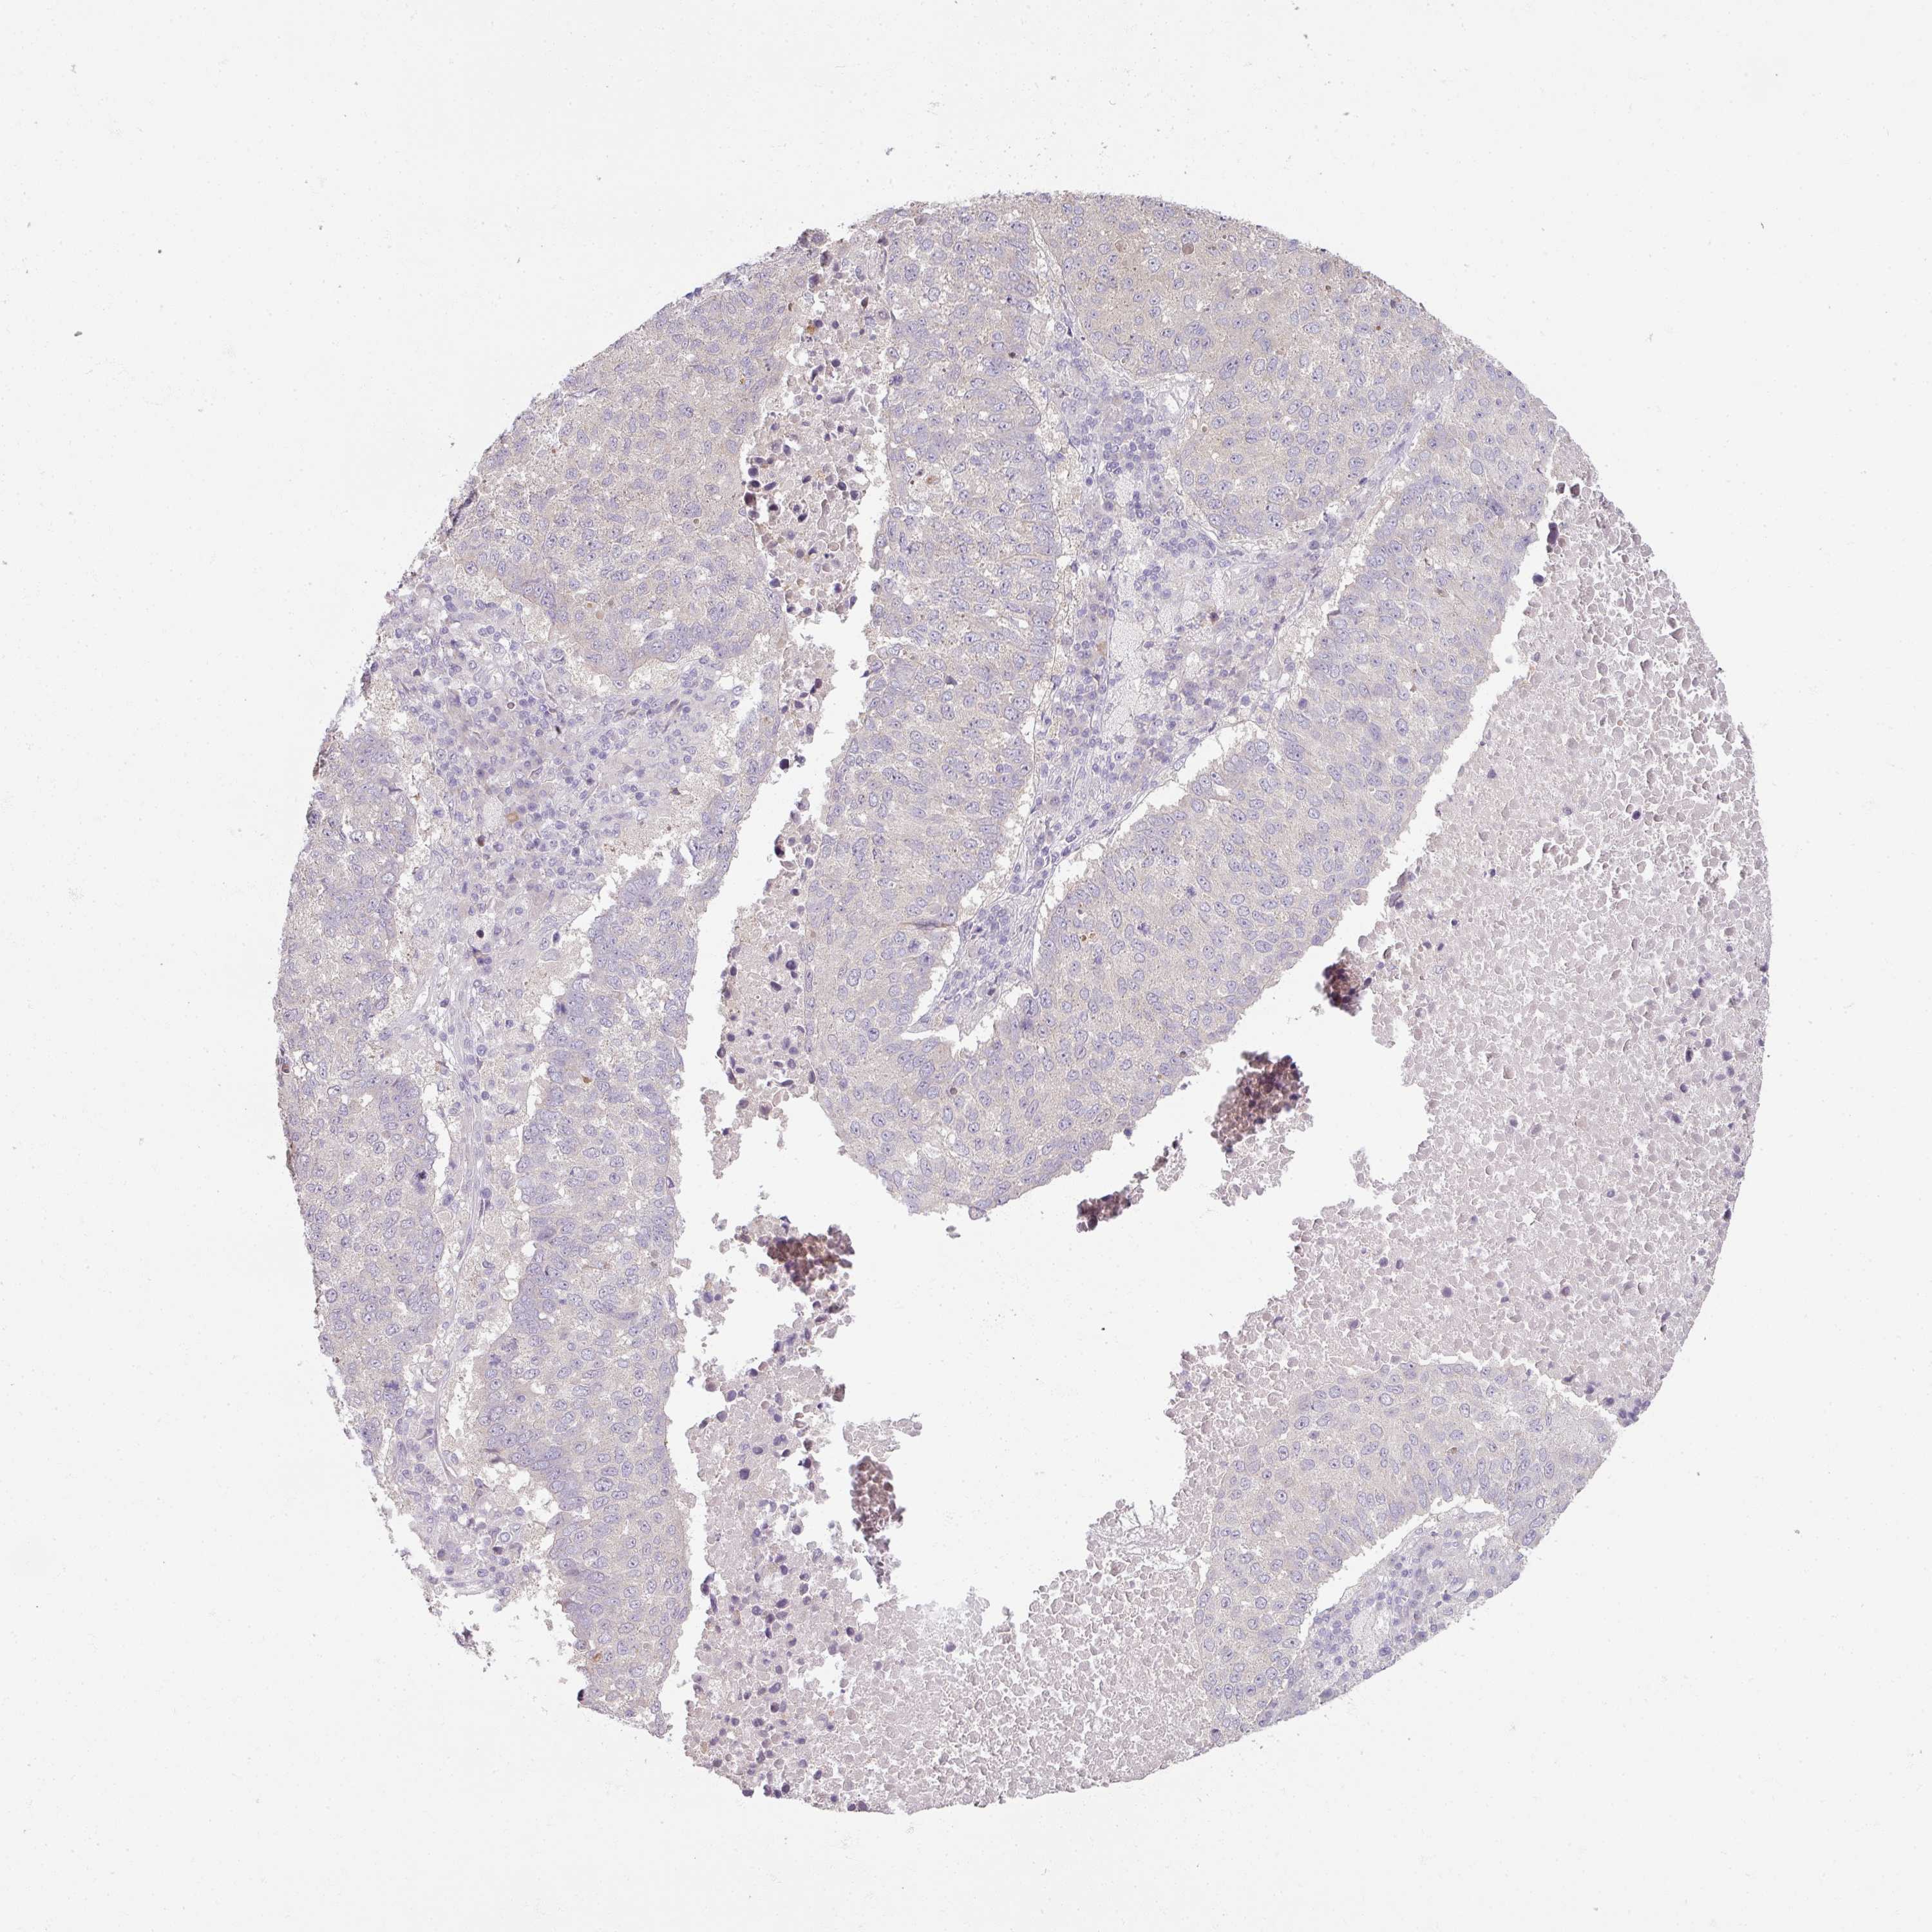

CANCER LUNG CANCER Show tissue menu

LUAD TCGA LUAD VALIDATION LUSC TCGA LUSC VALIDATION PROTEIN LUAD CPTAC PROTEIN LUSC CPTAC PROTEIN EXPRESSION